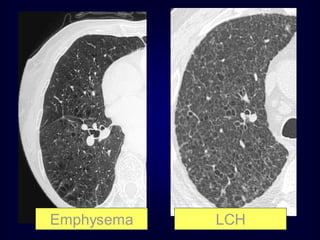

Emphysema

LCH

Clues to Diagnosis

Is there a wall ?

What is the shape and size ?

Smoker ?

Other signs

(e.g., bronchiectasis, pulmonary hypertension)